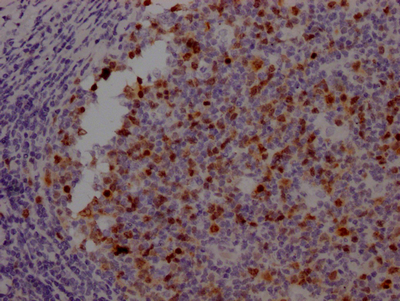

IHC image of CSB-RA230110A0HU diluted at 1:100 and staining in paraffin-embedded human tonsil tissue performed on a Leica BondTM system. After dewaxing and hydration, antigen retrieval was mediated by high pressure in a citrate buffer (pH 6.0). Section was blocked with 10% normal goat serum 30min at RT. Then primary antibody (1% BSA) was incubated at 4℃ overnight. The primary is detected by a Goat anti-rabbit IgG polymer labeled by HRP and visualized using 0.05% DAB.

IHC image of CSB-RA230110A0HU diluted at 1:100 and staining in paraffin-embedded human cervical cancer performed on a Leica BondTM system. After dewaxing and hydration, antigen retrieval was mediated by high pressure in a citrate buffer (pH 6.0). Section was blocked with 10% normal goat serum 30min at RT. Then primary antibody (1% BSA) was incubated at 4℃ overnight. The primary is detected by a Goat anti-rabbit IgG polymer labeled by HRP and visualized using 0.05% DAB.